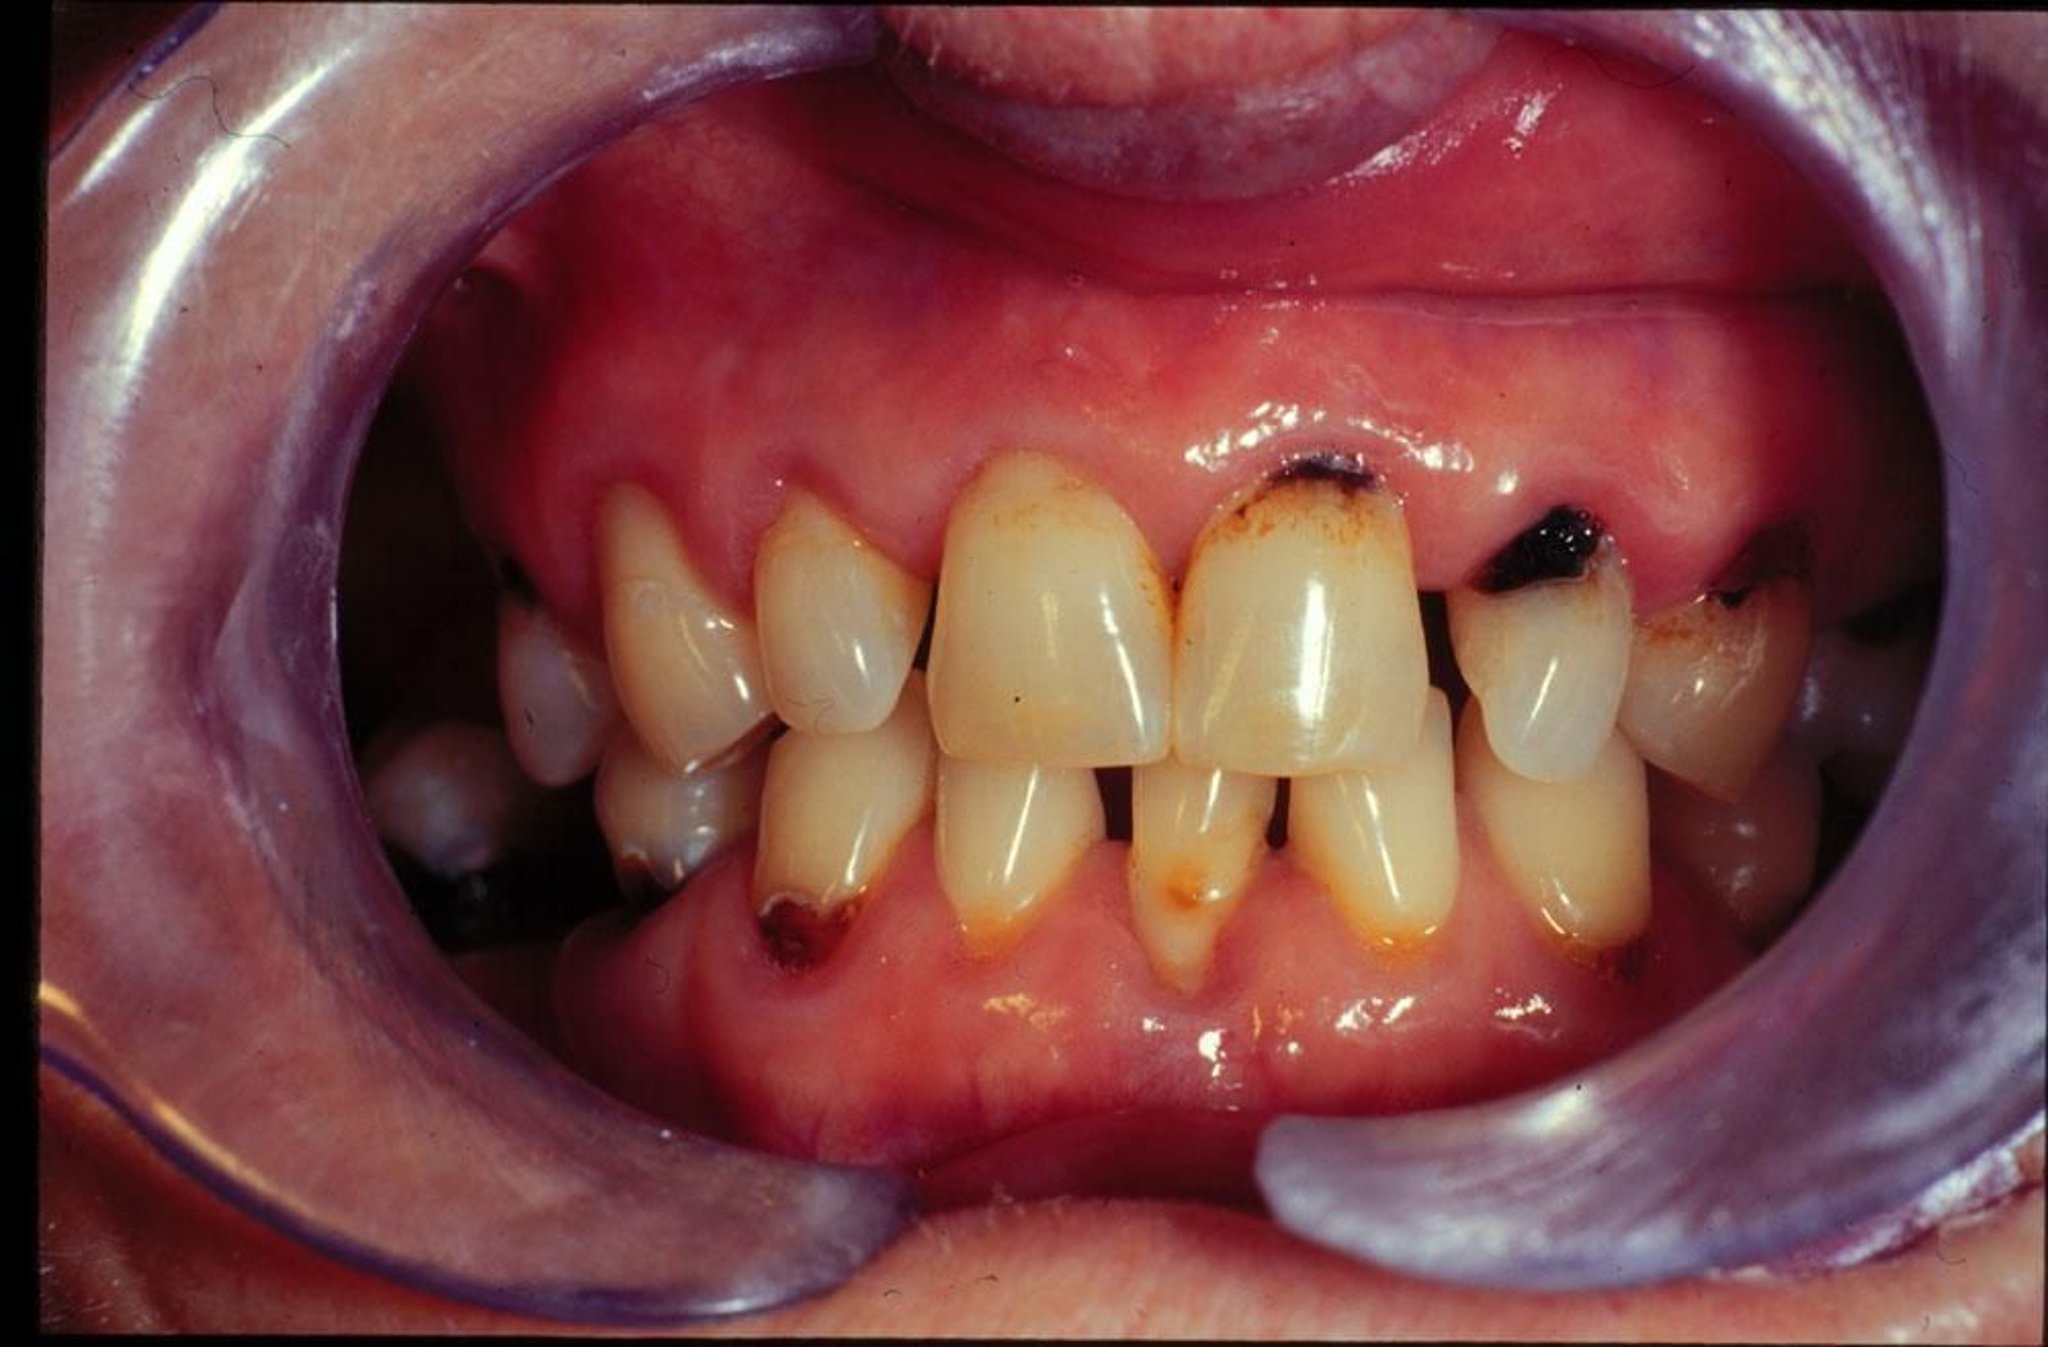

Esta imagem mostra cáries novas e recorrentes em uma pessoa com boca seca.

Imagem fornecida pelo Dr. Jonathan A. Ship, DMD.